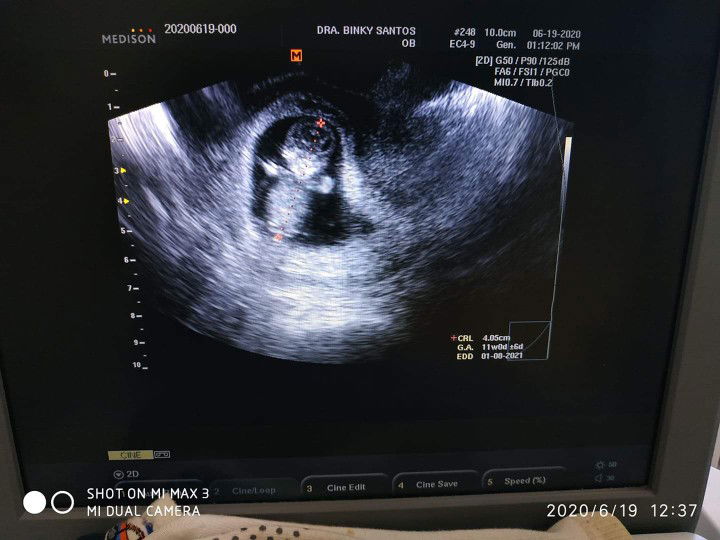

Ultrasound

Ask ko lang po TVS kc gnwa sakn, pero ang position ni baby nakatayo at nakaharap.. Ok lang kaya to common kc nakikita ko nakahiga ang baby sa ultrasound hehe